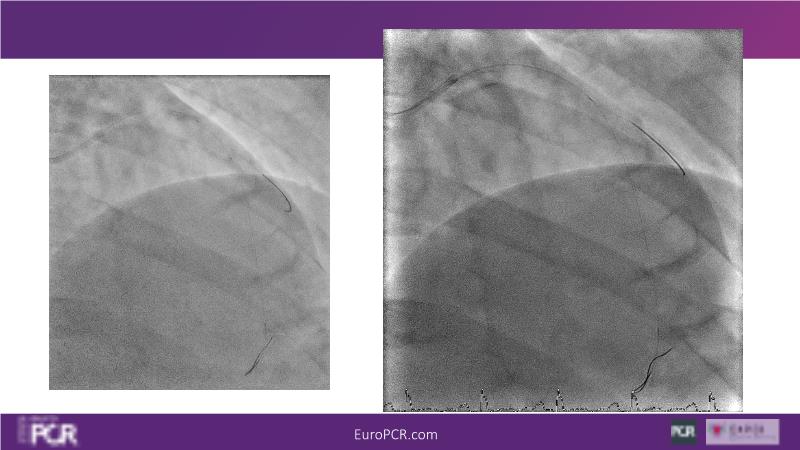

Join this session to delve into the unmet needs concerning drug-eluting stents (DES), including poor long-term clinical outcomes, with up to a 50% MACE rate at 10 years, and a non-plateauing 2-3% annual event rate. Explore how DynamX Bioadaptor technology addresses these challenges by maintaining the established flow lumen and restoring hemodynamic modulation of the artery. Discover the sustained clinical benefits demonstrated in a 2-year RCT, potentially establishing a new treatment standard for CAD patients. Gain insights into patient types benefiting most in clinical practice, such as those at higher risk of restenosis (e.g., LAD disease, long lesions, small vessels, co-morbidities), and younger patients with longer lifespans.